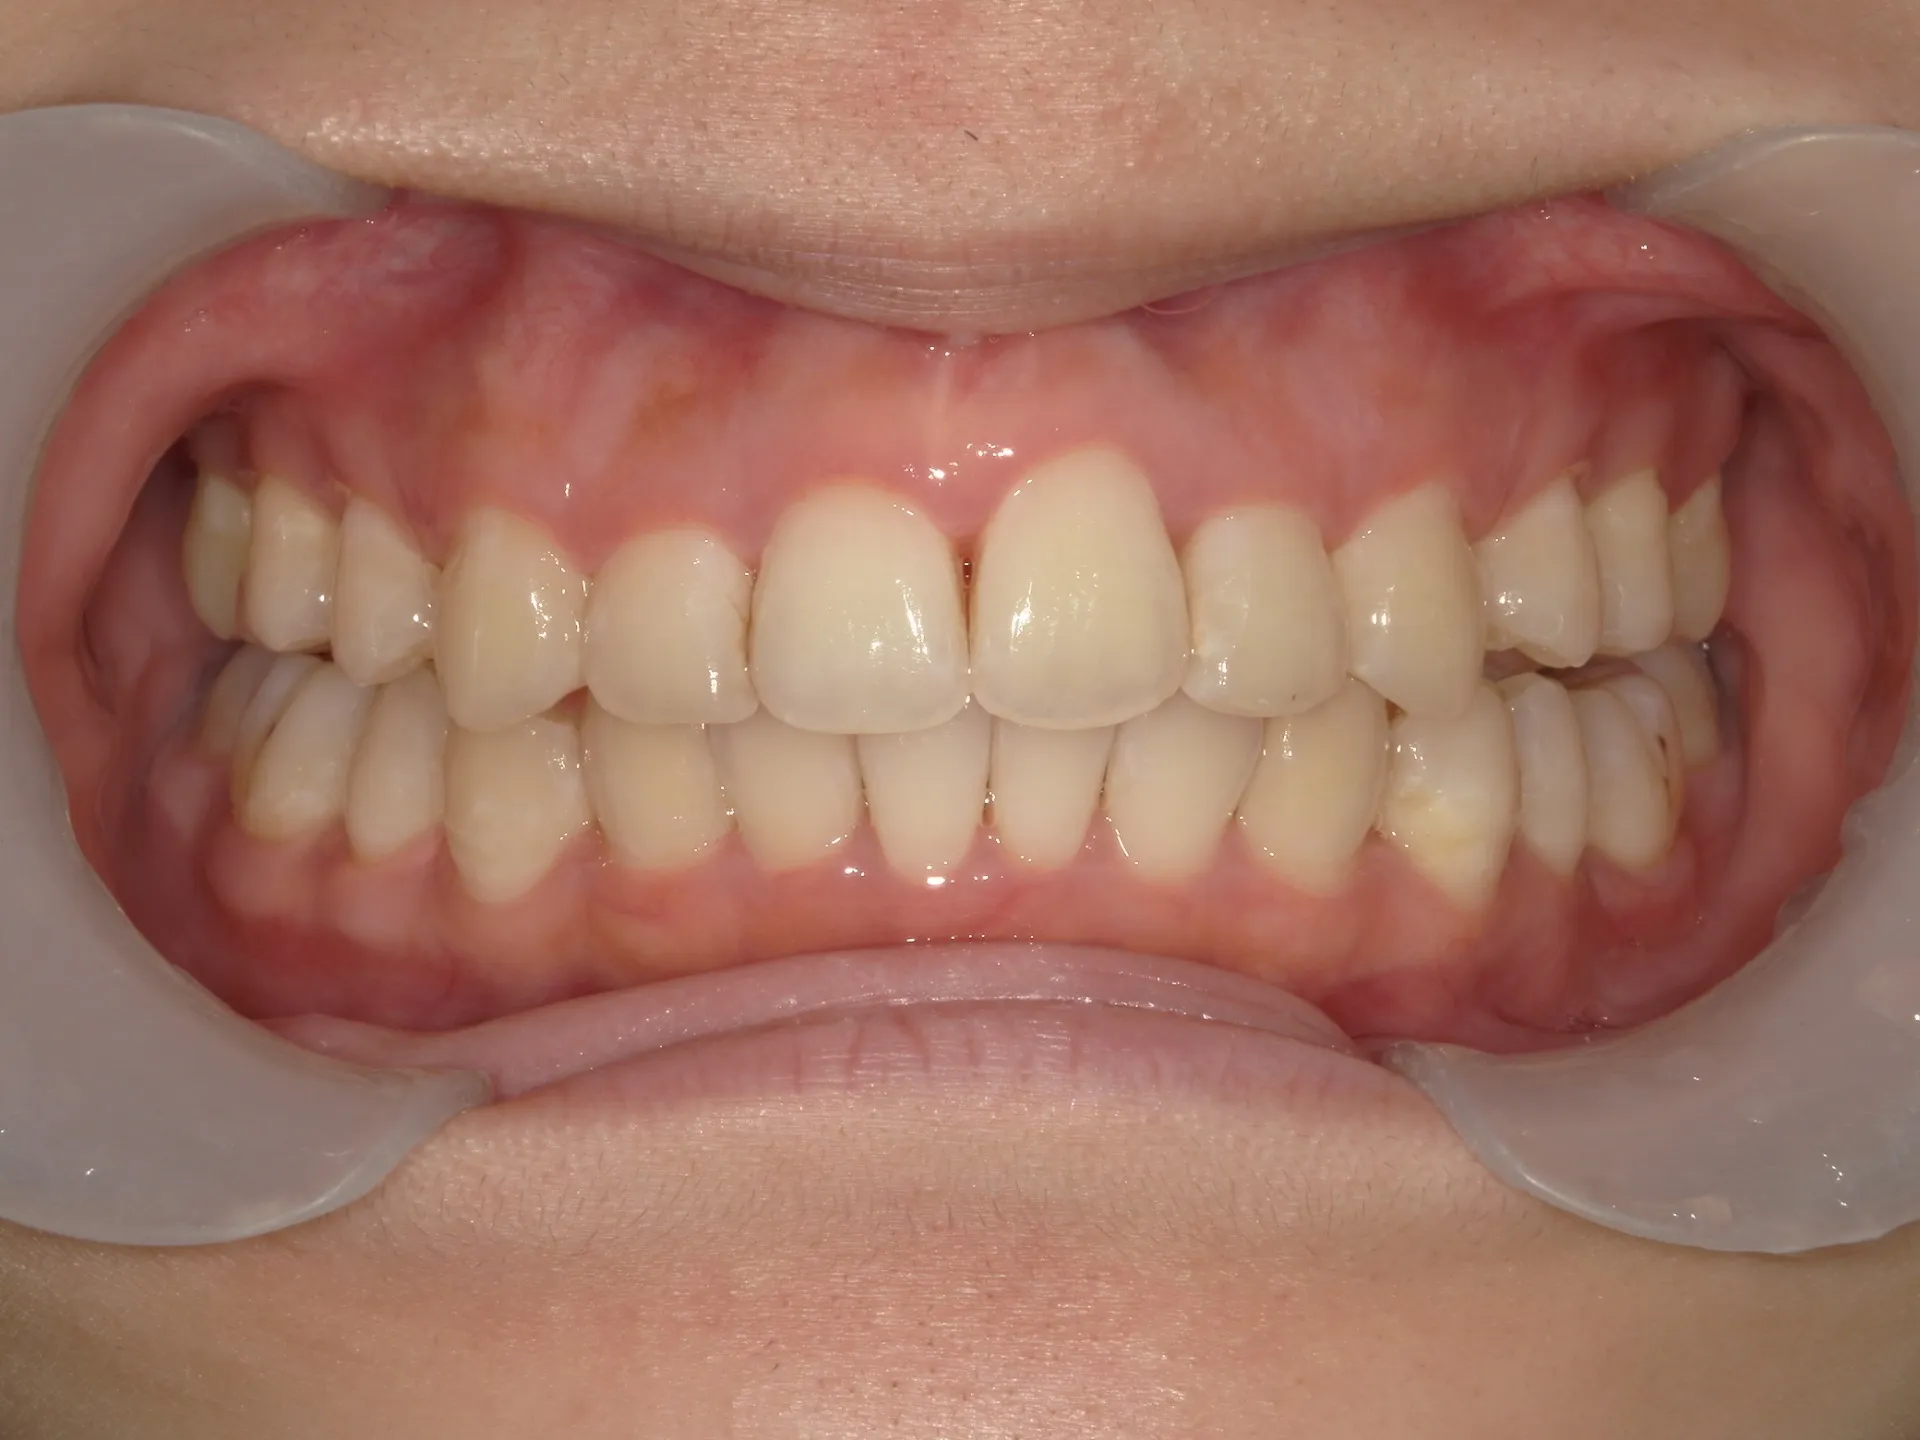

今回はマウスピース矯正(インビザライン)で前歯の出っ張りを治したケースをご紹介いたします。

マウスピース矯正で前歯の出っ歯感を抑えることが可能で、このケースでは上の歯のみ2本の抜歯を行っています。